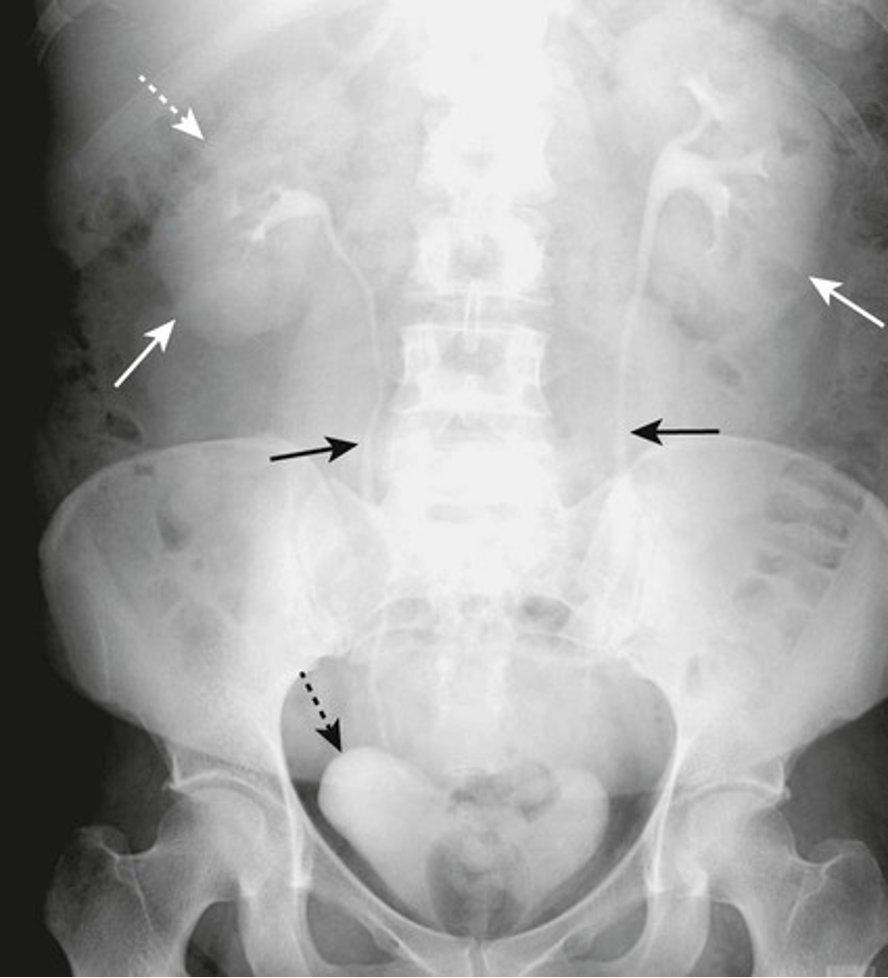

What is an abdominal aortic aneurysm (AAA)?

-enlargement of abdominal aorta

-Risk factors: HTN, atherosclerosis

-usually asymptomatic, but can cause pain

-large ones can rupture lead to hypotension and death

What is a calcified aortic aneurysm?

-common in those with DM and atherosclerosis

-aorta has rim like calcifications

-aneurysm is when normal diameter exceeds 50% of normal size